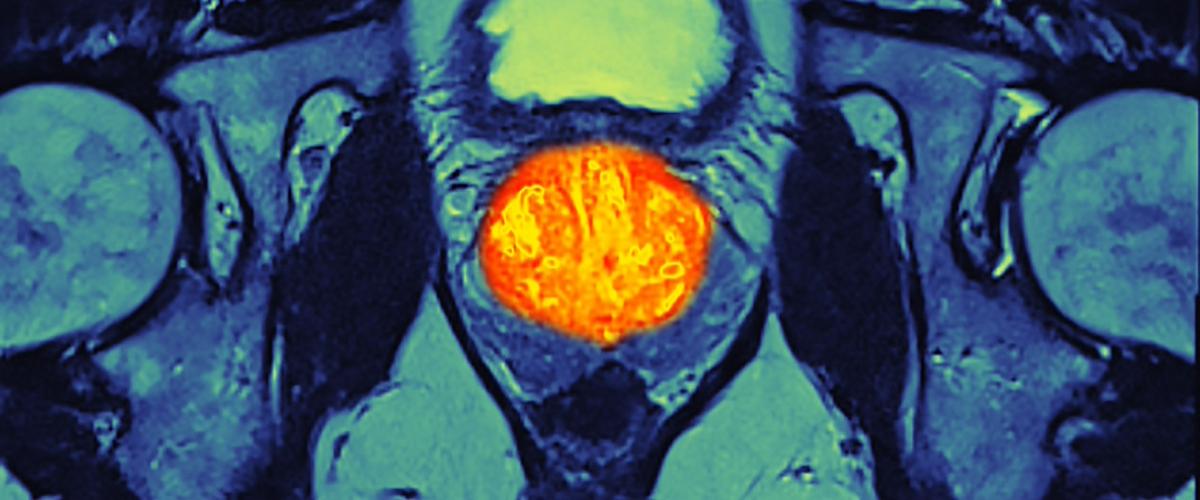

Канадские ученые провели анализ более чем 8000 тысяч злокачественных опухолей по 19 различным типам рака и обнаружили схожие признаки гипоксии. Авторы впервые определили молекулярные маркеры гипоксии опухолей, где главным образом изучался рак простаты, сообщается на сайте Института по исследованию рака в Онтарио.

В отличие от здоровых тканей, злокачественные опухоли процветают в среде с низким содержанием кислорода. В настоящее время влияние гипоксии на развитие опухоли изучено слабо, но выводы канадских ученых вносят большой вклад в этот пробел о природе рака.

Команда обнаружила общие молекулярные признаки гипоксии, которые могут помочь предсказать агрессивность опухоли, а значит — принять правильное решение по тактике лечения.

Выводы содержат данные по ряду генов, которые чаще других мутируют при гипоксии, а также информацию по моделям развития таких опухолей.

Ранее гипоксия ассоциировать с агрессивным течением рака, однако механизмы были плохо изучены с точки зрения генетики. Теперь ученые могут применять свои выводы в клинических исследованиях, чтобы одновременно выявлять признаки гипоксии и генетические мутации, и в результате применять индивидуальные решения для лечения конкретного пациента.

«Изначально мы планировали изучить отличия между агрессивным и неагрессивным раком предстательной железы, однако новые выводы открывают возможности для выбора методов лечения и для многих типов опухолей», — заключает старший автор исследований Пол Бутрос.